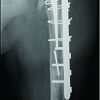

The post-operative period was uneventful. We removed K wires at four weeks and started elbow mobilization. At the end of 3 months, a full range of movements was present, and the fracture showed good callus bridging over the medial and lateral metaphysis on the radiograph (Fig. 4).